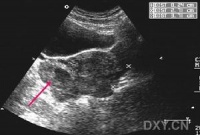

大多起病缓慢,迷走神经切断术者常于术后第2周开始进流质饮食后发病。主要症状有腹胀、上腹或脐周隐痛,恶心和持续性呕吐。呕吐物为混浊的棕绿色或咖啡色液体,呕吐后症状并不减轻。随着病情的加重,全身情况进行性恶化,严重者可出现脱水、碱中毒,并表现为烦躁不安呼吸急促、手足抽搐血压下降和休克。突出的体征为上腹膨胀,可见毫无蠕动的胃轮廓,局部有压痛叩诊过度回响,有振水声。脐右偏上出现局限性包块,外观隆起,触之光滑而有弹性、轻压痛,其右下边界较清,此为极度扩张的胃窦,称“巨胃窦症”,乃是急性胃扩张特有的重要体征,可作为临床诊断的有力佐证。